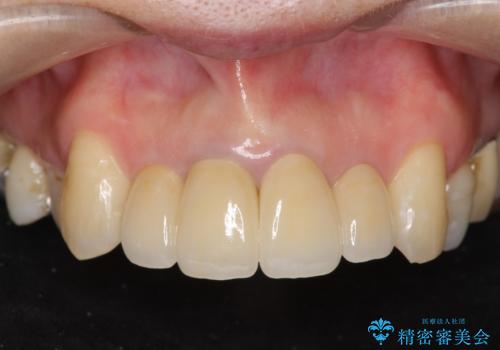

![[ 前歯が割れた ] ブリッジによる審美回復治療の症例 治療後](https://seimitsushinbi.jp/wp/wp-content/uploads/2019/11/486ebd7e0fd0fbcf4a4611c722fe431f-500x350.jpg?v=1574859391)